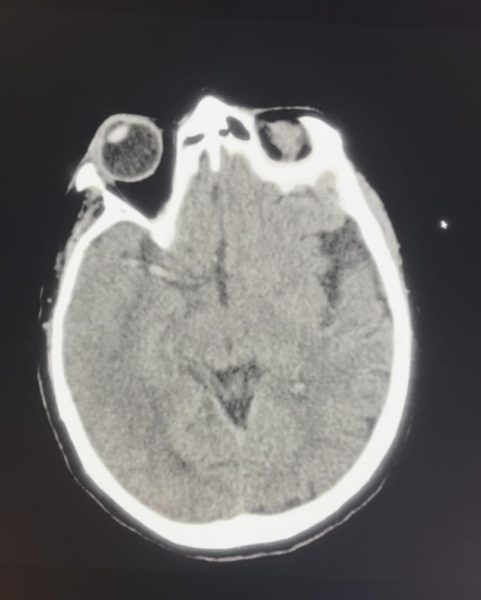

Pela importante suspeita clínica de acidente vascular cerebral, foi iniciado protocolo com realização de tomografia computadorizada, sem sangramentos e estando presente o seguinte achado:

Qual o sinal evidente da tomografia de crânio?

ASinal do delta vazio

DSinal da artéria cerebral média hiperdensa